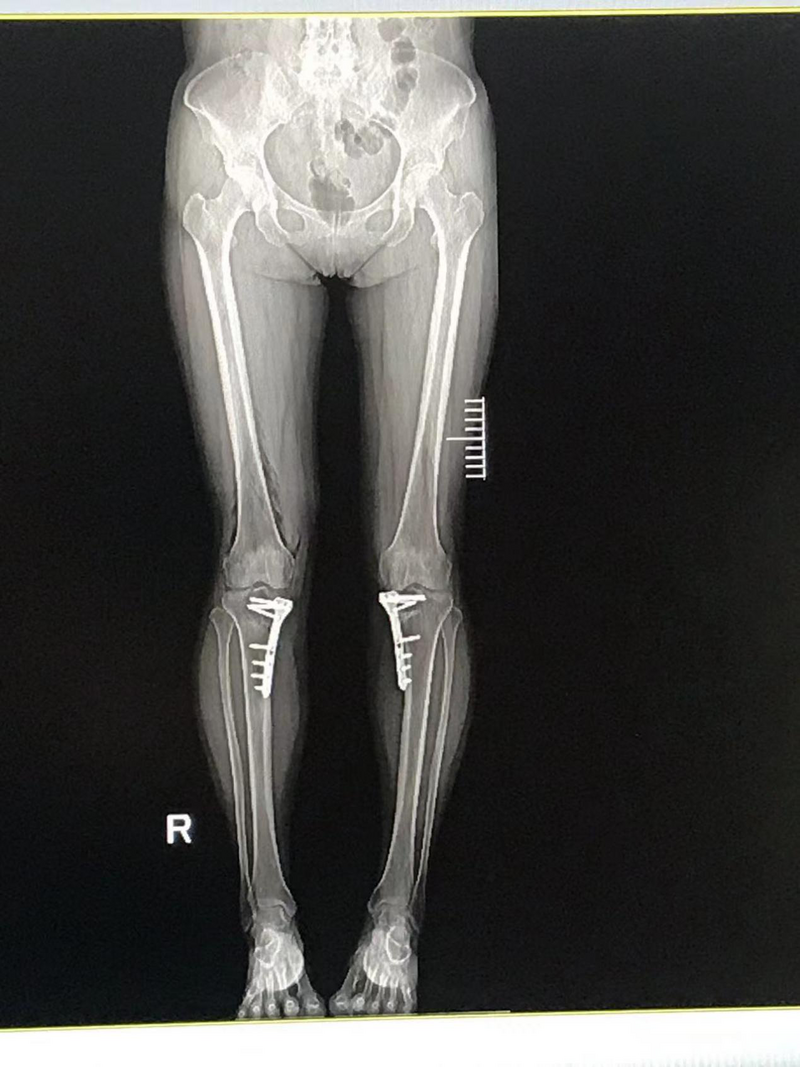

手術(shù)后患者雙膝內(nèi)翻畸形得到糾正

手術(shù)后患者切口微創(chuàng),可早期下地行走,效果滿意。